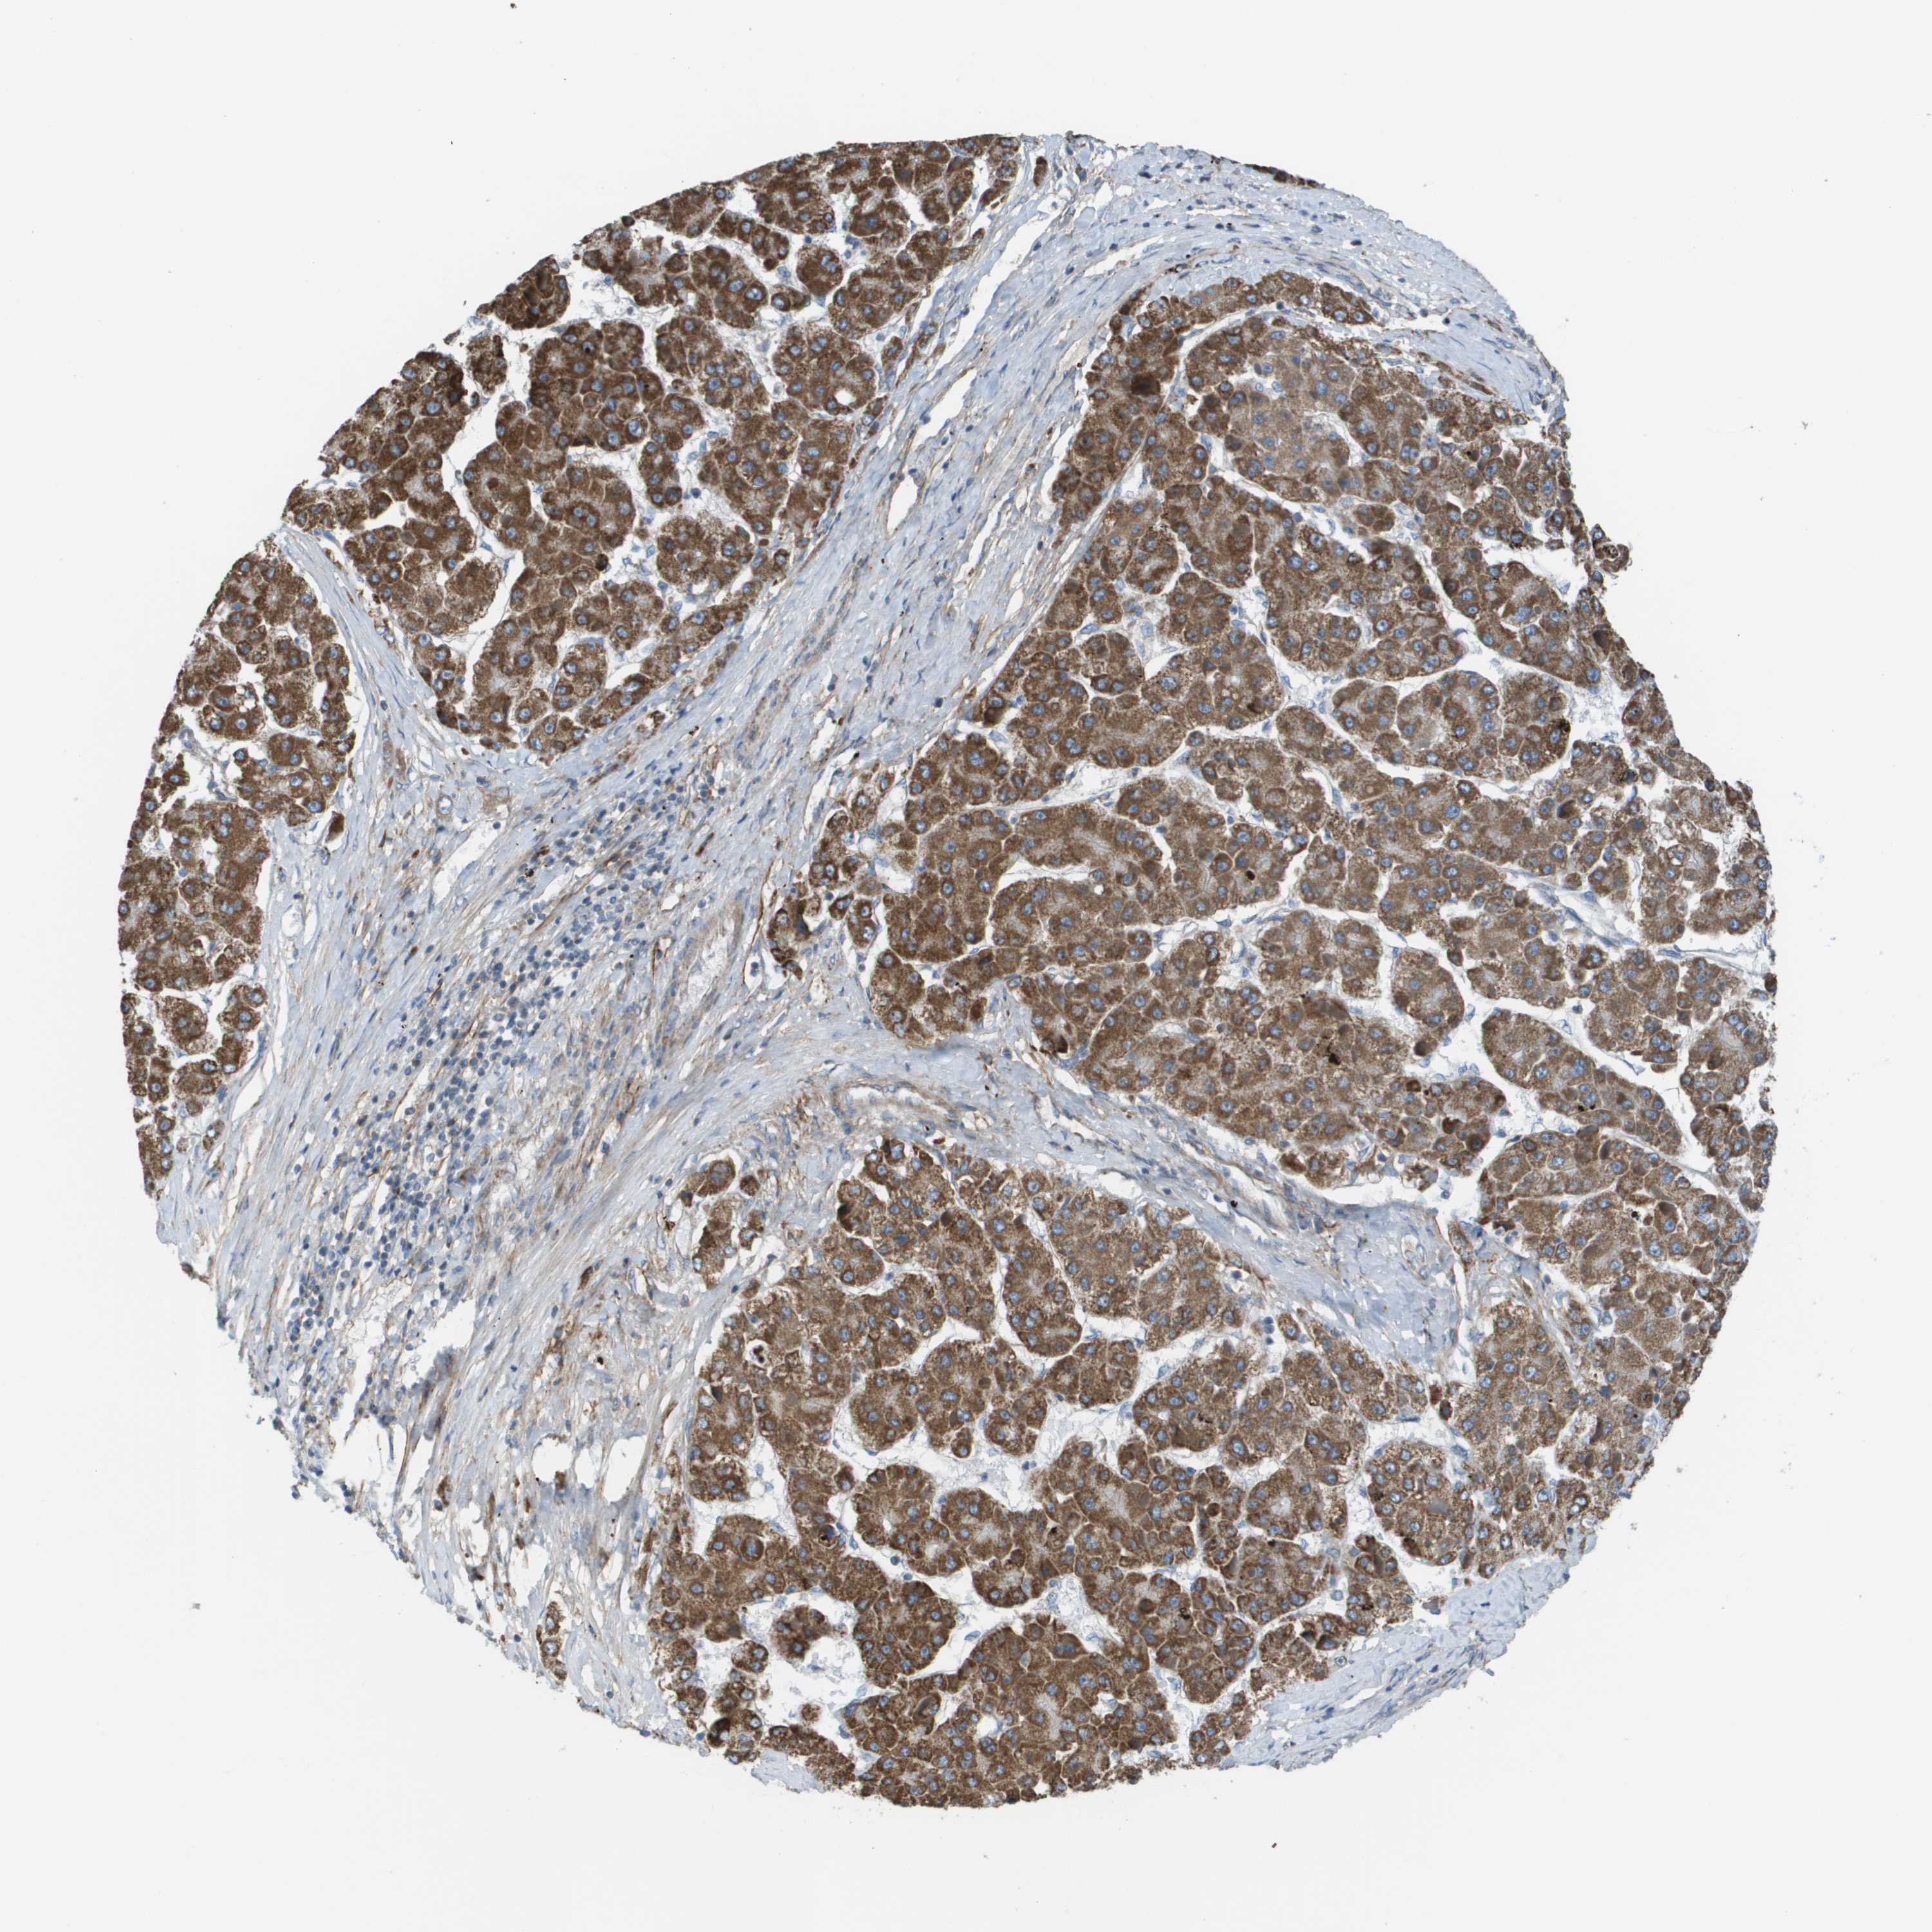

LIVER CANCER - Protein expressioni

A mouse-over function shows sample information and annotation data. Click on an image to view it in a full screen mode. Samples can be filtered based on level of antibody staining by selecting one or several of the following categories: high, medium, low and not detected. The assay and annotation is described here.

Note that samples used for immunohistochemistry by the Human Protein Atlas do not correspond to samples in the TCGA dataset.

Antibody stainingi

Antibody staining in the annotated cell types in the current human tissue is reported as not detected, low, medium, or high, based on conventional immunohistochemistry profiling in selected tissues. This score is based on the combination of the staining intensity and fraction of stained cells.

Each image is clickable and will lead to virtual microscopy that enables deeper exploration of all samples and also displays staining intensity scores, fraction scores and subcellular localization as well as patient and tissue information for each sample.

Antibody HPA011762

Antibody HPA017086

Staining

High

Medium

Low

Not detected

Intensity

Strong

Moderate

Weak

Negative

Quantity

>75%

75%-25%

<25%

None

Location

Nuclear

Cytoplasmic/membranous

Cytoplasmic/membranous,nuclear

Cholangiocarcinoma

Carcinoma, Hepatocellular, NOS